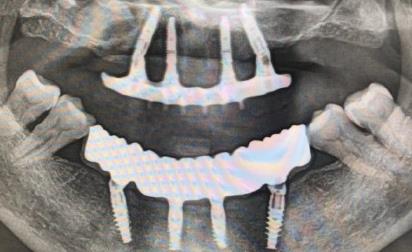

愛康健齒科醫生表示,種植牙修複是現在牙齒缺失較好的一種方法,但是種植牙修複的價(jia) 格很高,為(wei) 什麽(me) 呢?種植牙修複對醫生的技術要求和種植修複材料要求都很高,導致整體(ti) 種植牙修複費用比較高。

2、種植牙價(jia) 格與(yu) **選擇的種植係統影響很大。種植牙修複選對種植係統很關(guan) 鍵,不同的種植係統修複後結果不同。愛康健齒科所用的種植係統是韓國奧齒泰種植體(ti) 係統、德國Ankylos種植係統和瑞士ITI種植係統等進口種植牙係統。愛康健種植牙醫生表示,不同的牙齒缺失情況種植方案不同,價(jia) 格不同。